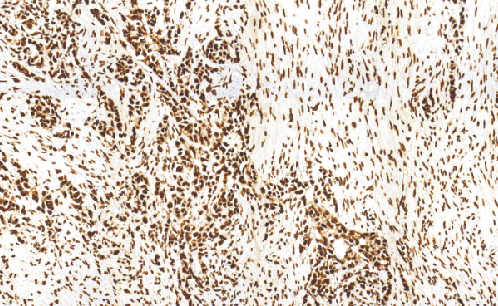

CDK4兔抗人CDK4单克隆抗体

细胞周期蛋白依赖性激酶4(CDK4)是丝氨酸/苏氨酸蛋白激酶家族的成员之一,它是蛋白激酶复合体的催化亚基,对细胞周期G1期的发展起着重要的作用。据报道,在许多肿瘤中,都可以检测到CDK4的过表达,如口腔鳞状细胞癌、胰腺癌(内分泌肿瘤)、肺癌、乳腺癌和结肠癌。CDK4的表达与肿瘤的发展有关。

- 阳性部位:胞核

- 适用组织:石蜡切片

- 预处理:热修复